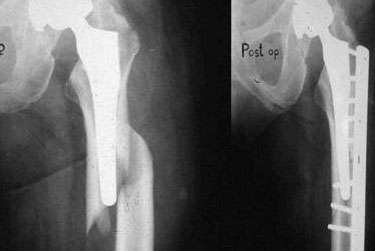

Dr Prateek Kumar is a highly qualified compassionate orthopaedic surgeon with over 15yrs of experience in field of Orthopaedic & Arthroplasty.He has received his medical education from renowned Institutions in India & has continuously updated his knowledge to stay at the forefront of medical advancement. Dr.Prateek Kumar is committed to providing the best possible care to his patients ensuring their comfort and well being throughout their treatment.